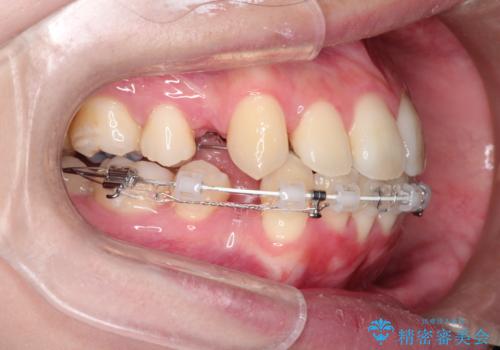

口元が出てるの気になる ハーフリンガルによる抜歯矯正での横顔改善

- 前歯が出ているため口が閉じにくく、横顔が気になるとのことで来院された患者様です。。

上下の前歯が前方に傾斜しており、口唇の突出感がありました。

上下左右の前から4番目の歯を抜歯して、上下の前歯を後方に移動させる計画としました。

抜歯矯正により、前歯をしっかり下げることで口元がすっきりしました。